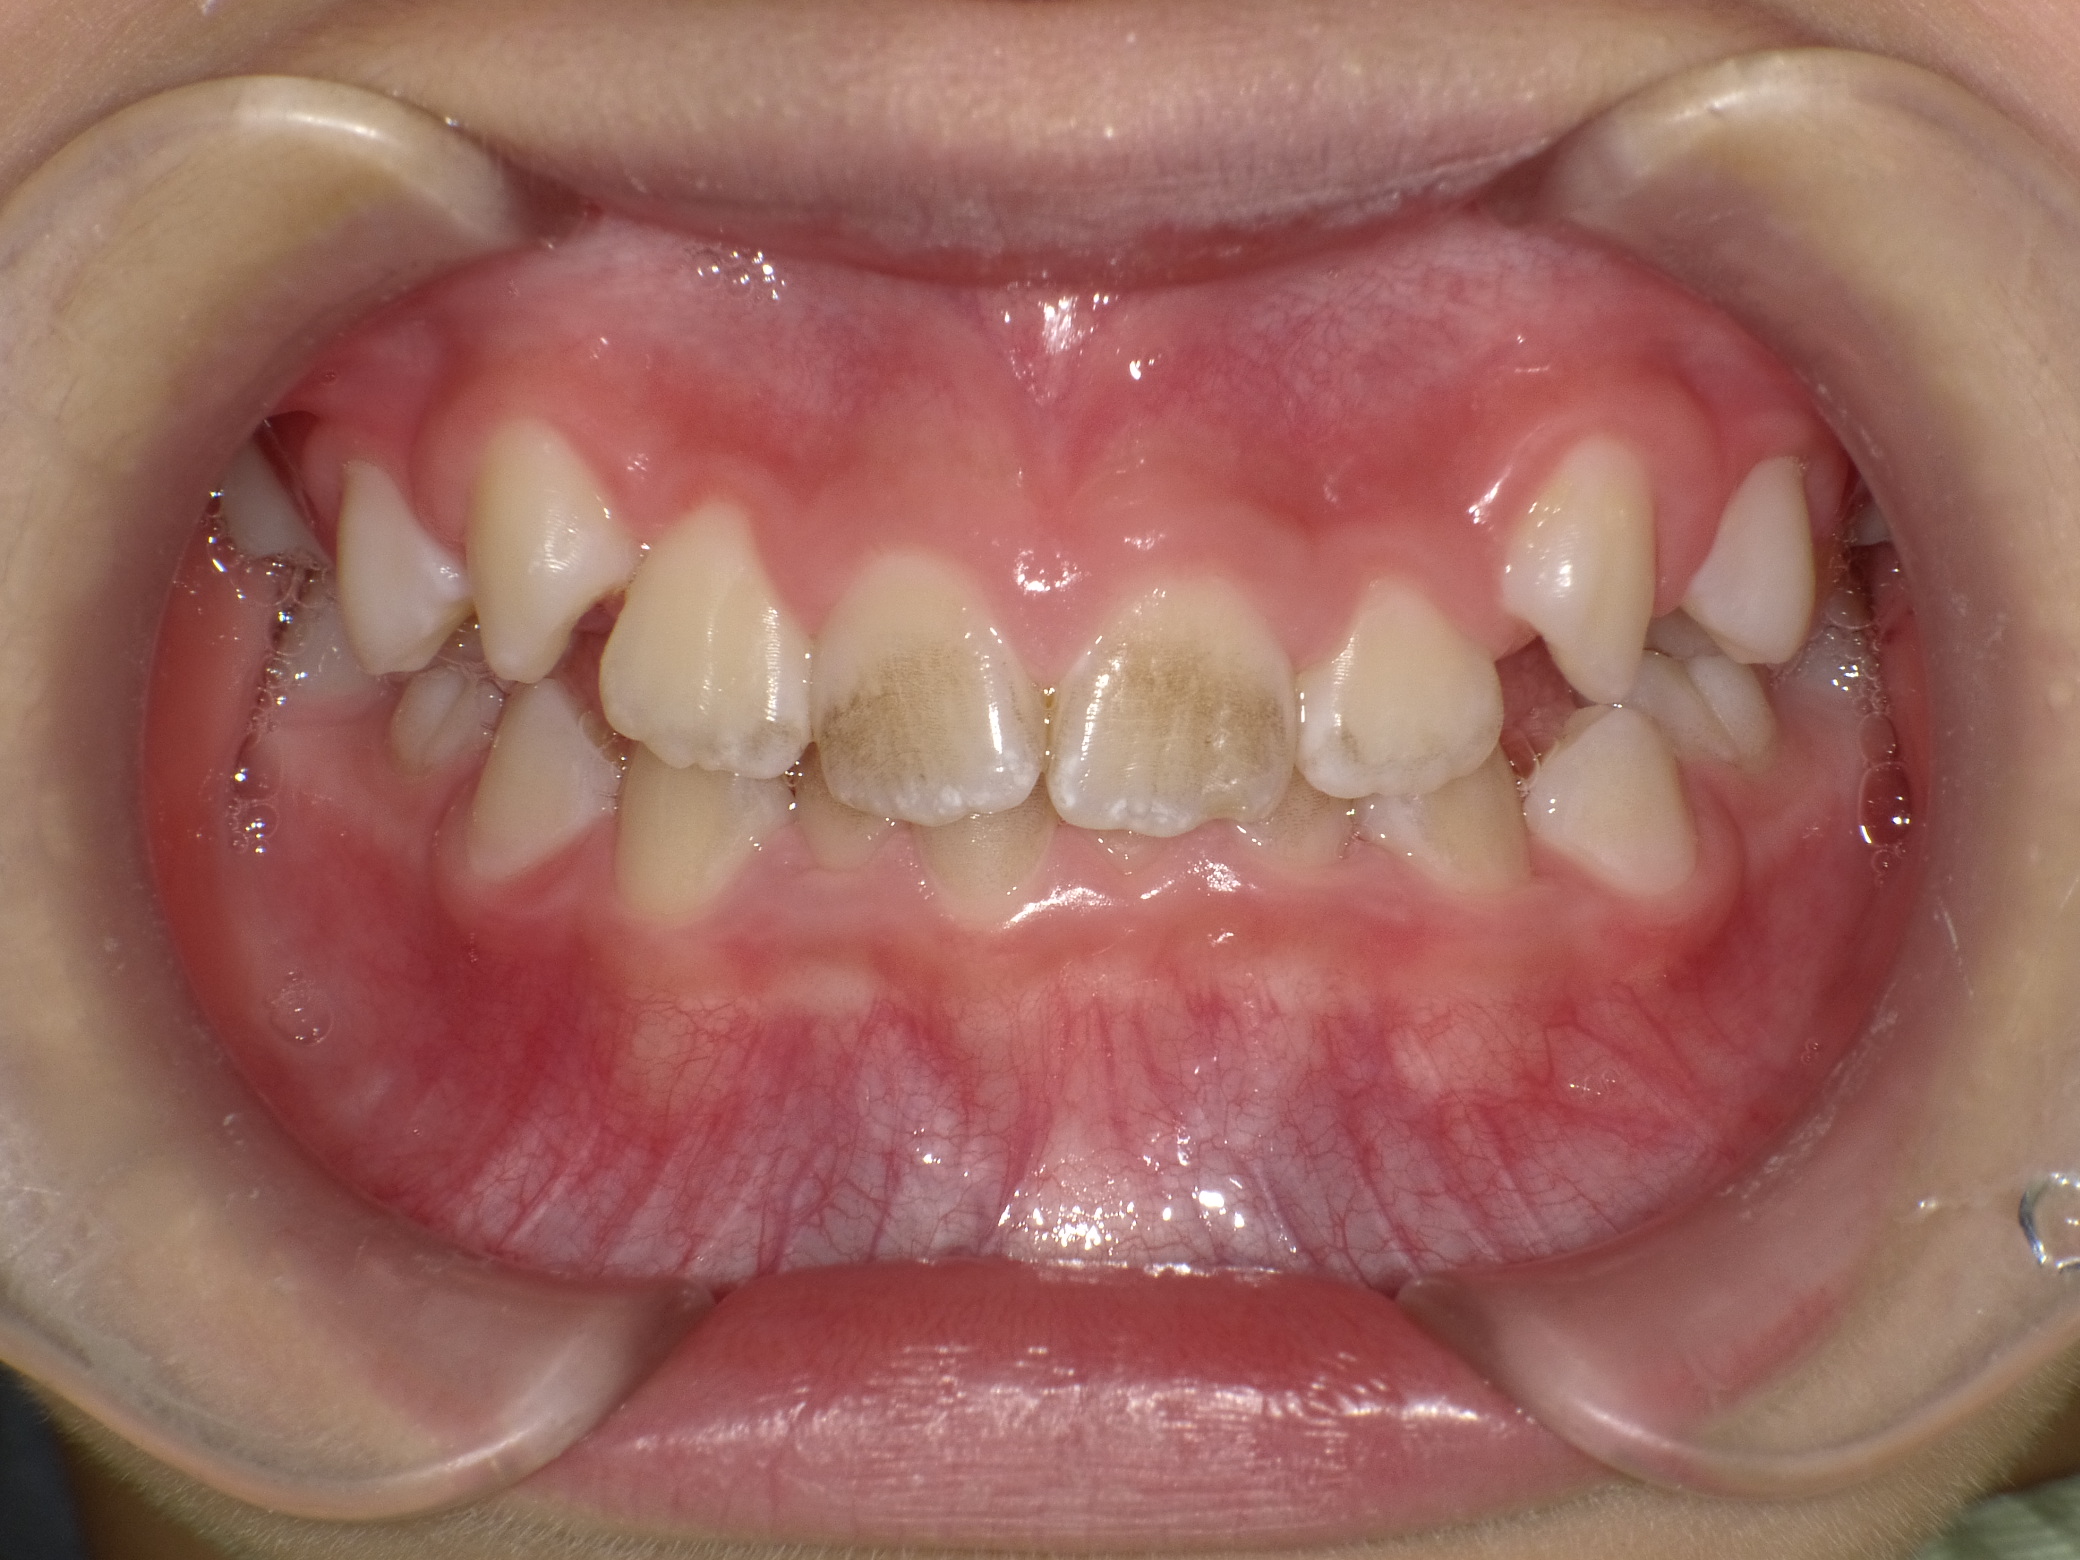

Before

でこぼこ

過蓋咬合

非抜歯

1期治療のみで改善